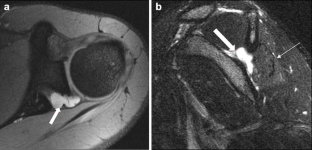

Fig. 2